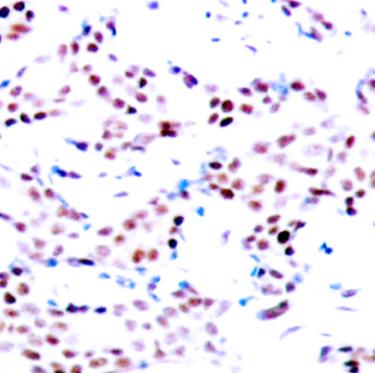

Formalin-fixed;paraffin-embedded human breast carcinoma tissue stained for c-Jun (Phospho-T91) using 13420 at 1/100 dilution in immunohistochemical analysis.